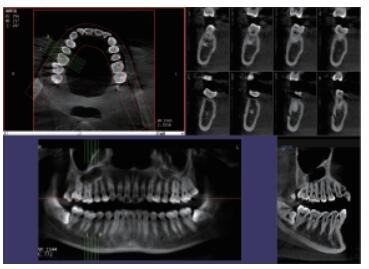

三維重建任意斷層

專有三維重建算法,可提供任意位置高清斷層影像。

高清口腔全景影像

通過(guò)三維容積影像,提取高清口腔全景影像。

多平面組合重建

可同時(shí)觀察軸向面、冠狀面和矢狀面圖像,方便臨床診斷。